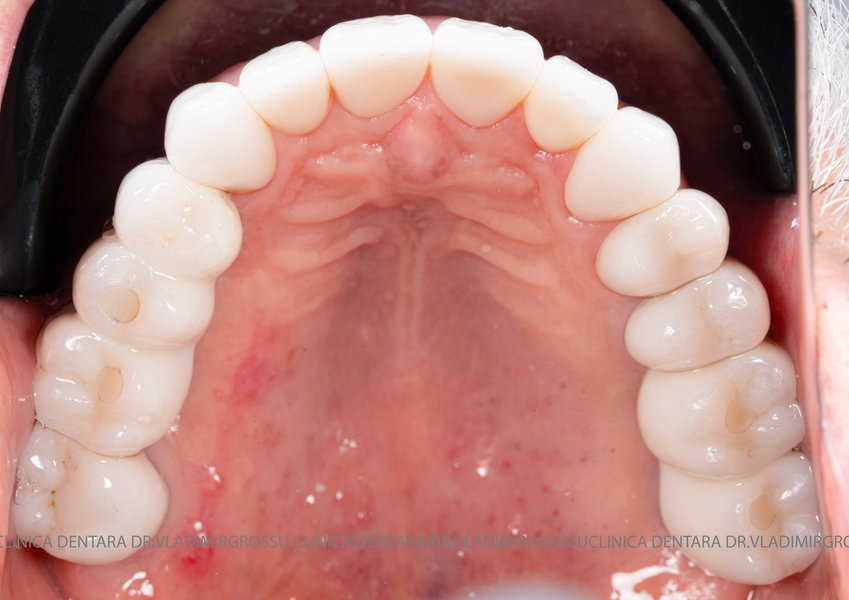

Aditia gingivală este o procedură chirurgicală ce corectează diverse probleme estetice și funcționale, cum ar fi recesiunea gingivală. În implantologia modernă, aditia de țesut moale este utilizată aproape în fiecare intervenție de inserție a implantului dentar pentru a asigura un aspect estetic natural și o bună integrare a implantului în cavitatea bucală.

Adiția osoasă are un rol crucial pentru poziționarea corectă și stabilă a implanturilor dentare. Clinica stomatologică Dr. Grossu din Chișinău promovează o abordare chirurgicală estetică și predictibilă, adaptată fiecărui caz în parte.

Medicii noștri au o vastă experiență atât în chirurgia estetică, cât și în protezarea cu un grad înalt de naturalitate, ceea ce ne permite să gestionăm cu succes și cele mai complexe cazuri.